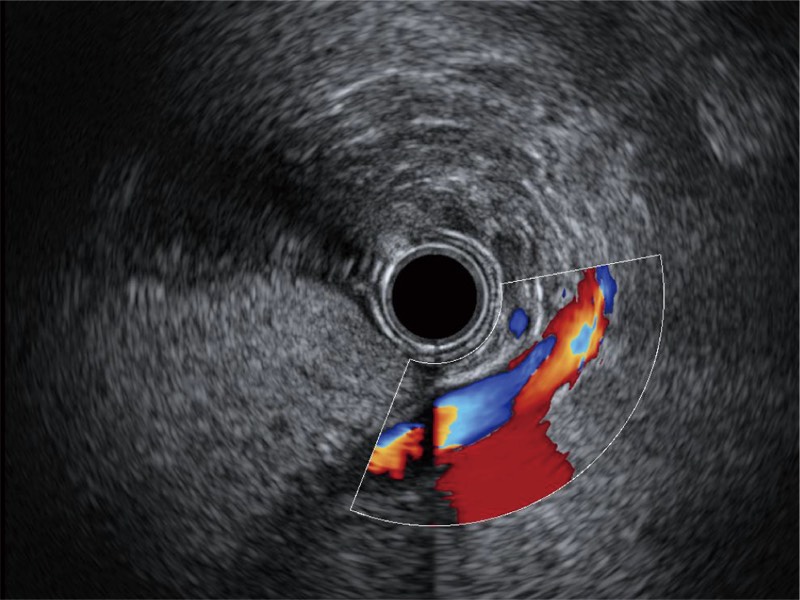

清晰顯示膽總管及周圍血管分布